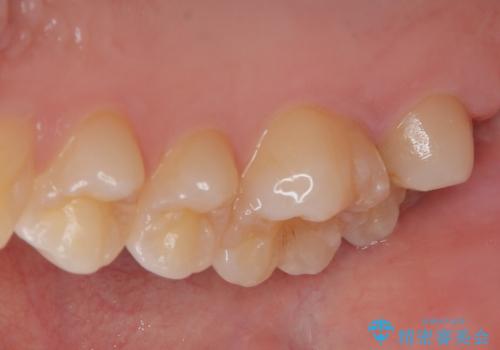

ゴールドインレー(PGAインレー)はセラミックインレーと比べ、歯の切削量が少なく、適合性が著しくいいことが特徴です。上顎の奥歯は見えないので機能面でゴールドインレー、ゴールドクラウンはおすすめです。

違和感がないと喜んでいただきました。